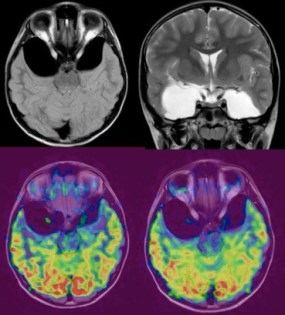

A : méga-grande citerne ; B : Dandy-Walker ; C : récessus pinéal ; D : porencéphalie - on demande également à l’imagerie de dire si le kyste est compressif ou non, ce qui est souvent difficile à déterminer. de nouvelles techniques d’imagerie comme l’ASL (Arterial Spin Labelling) sont encours d’évaluation dans la prise en charge des kystes arachnoïdiens.

les différentes techniques d’imagerie ont chacune des avantages et des inconvénients, et donc des indications respectives.